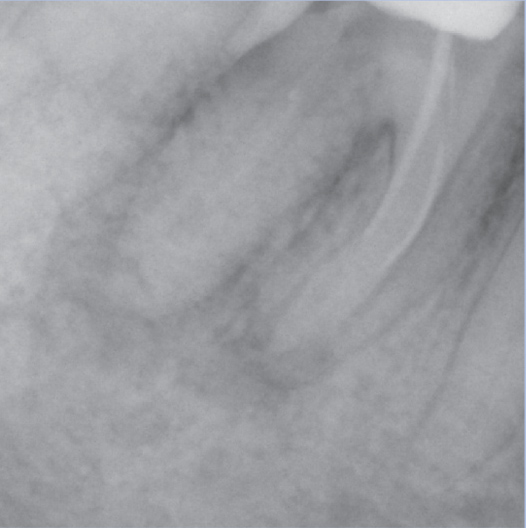

Before

Before Root Canal treatment